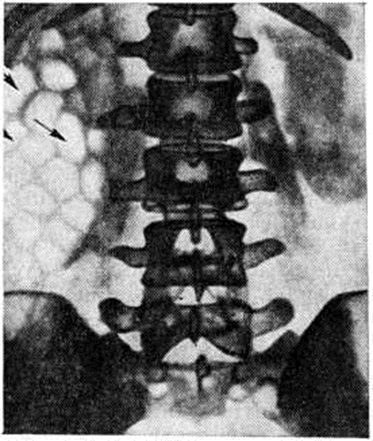

Эмфизематозный пиелонефрит — одна из форм острого гнойного Пиелонефрит Наблюдается преимущественно у больных сахарным диабетом, несколько чаще у женщин. Возбудителями являются кишечная палочка, В. aerogenes, протей, стафилококк и другие Возникновению эмфизематозного Пиелонефрит способствуют наличие в организме анаэробных микроорганизмов, обструкция мочевых путей. Заболевание обычно поражает одну почку и нередко сочетается с некрозом почечных сосочков, тромбозом почечной вены. Характерен некроз паренхимы почки с образованием газа внутри органа и в околопочечной клетчатке. Высокое содержание глюкозы в крови при сахарном диабете является дополнительным фактором, обусловливающим выработку углекислого газа. Болезнь протекает тяжело, сопровождается состоянием, напоминающим ступор, интоксикацией, почечной недостаточностью, высокой температурой, сильными болями в поясничной области, лейкоцитозом, Лейкоцитурией, бактериурией. Моча имеет резко кислую реакцию. В распознавании эмфизематозного Пиелонефрит большую роль играют рентгенологическое методы исследования, в частности обзорный снимок, компьютерная томография. На рентгенограмме в проекции почки видно скопление теней газовых пузырей (рисунок 2). При бактериологические исследовании мочи находят газообразующие микроорганизмы.

Ведущее значение в распознавании хронический Пиелонефрит имеют методы рентгенологическое исследования. При обзорной урографии (смотри полный свод знаний) может быть отмечено уменьшение размеров и уплотнение тени поражённой почки. Это более отчётливо выявляется при экскреторной, особенно инфузионной, урографии. Уменьшение длины одной из почек более чем на 1 сантиметров, высокое, вертикальное положение органа подозрительны в отношении нефросклероза, перинефрита. Функциональные и органические изменения верхних мочевых путей проявляются наличием стойких спазмов и сужений шеек чашечек, атрофией почечных сосочков, вследствие чего чашечки приобретают грибовидную, колбовидную форму. Возникновение свежего воспалительного инфильтрата приводит к сдавлению и раздвиганию чашечек. В зоне нефросклероза происходит сближение чашечек и удлинение их шеек. Неравномерность поражения паренхимы почки при хронический Пиелонефрит часто выражается в появлении характерного симптома, описанного Ходсоном (С. G. Hodson): на урограмме нормальной почки линия, проведённая через вершины всех почечных сосочков, проходит параллельно наружному контуру тени почки; при хронический Пиелонефрит некоторые чашечки вследствие нефросклероза приближаются к латеральному краю почки, другие смещаются рубцами в сторону лоханки. Таким образом, соединяющая вершины сосочков линия становится волнообразной и не параллельна наружному контуру почки. Лоханка почки при хронический Пиелонефрит часто расширена, атонична, из-за этого на её медиальной поверхности обнаруживается отпечаток наружного края большой поясничной мышцы (краевой псоас-симптом). Степень уменьшения объёма почечной паренхимы и дилатации лоханочночашечной системы может быть более точно определена при расчёте ренокортикального индекса (частное от деления произведения длины лоханочно-чашечной тени и её ширины на произведение длины и ширины тени всей почки); в норме он равен 0,38—0,4. Для хронический Пиелонефрит характерны более высокие значения.